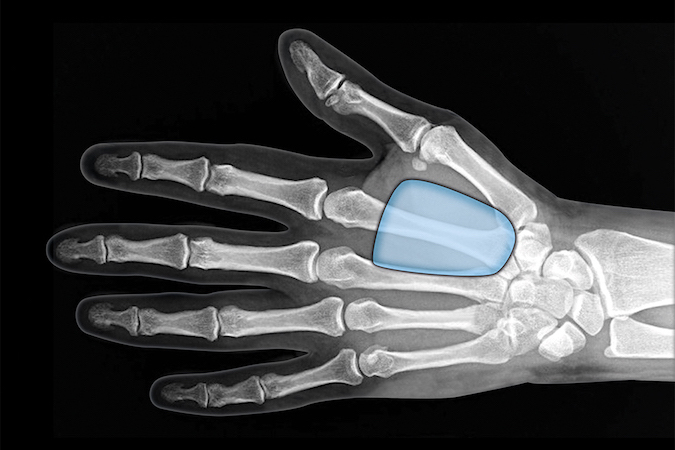

- Constricts of the flexor sheath at the A-1 level (section7) can cause trigger finger problems.

- When a trigger finger is present there is tenderness at the A1 pulley area with catching, crepitus, and/or locking of the finger during active motion.

- When a trigger finger is surgically released, the A-1 pulley in section 7 is cut longitudinally.

- During trigger finger release only the A1 pulley should be released in order to avoid bowstring of the flexor tendons.